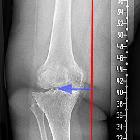

Genu valgum (layperson term: knock-knee) denotes the valgus deformity of the knee, where the lower leg is bending outwards in relation to the axis of the femur.

The valgus deformity can be quantified with the hip-knee-ankle angle (HKA), which measures the angle between the mechanical axis of the femur and the center of the ankle joint on AP, full-length, weight-bearing radiographs. The first line is drawn between the center of the femoral head and the femoral intercondylar point, while the second line runs from the tibial interspinous point to the tibial mid-plafond point. The angle between these lines determines the hip-knee-ankle angle. The normal range is varying due to the physiologic varus angle in infants, and physiologic valgus configuration in young children, but is generally 1-1.5° in healthy adults .